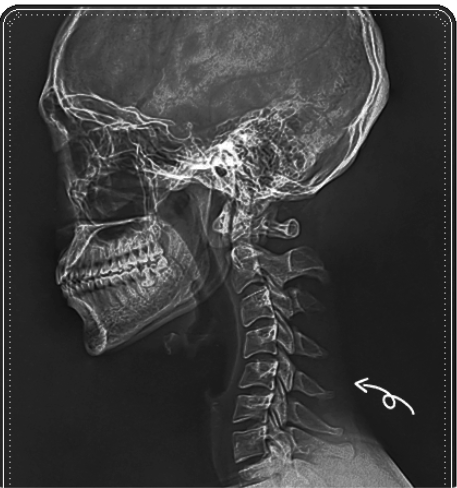

평소 어깨가 자꾸 앞으로 말리고, 목이 앞으로 나가는 느낌을 받으신 적 있으신가요?

왜 거북목과 굽은등은 쉽게 반복될까요?

굽은 등과 거북목은 단순히 ‘잘못된 자세’ 때문만은 아닙니다.